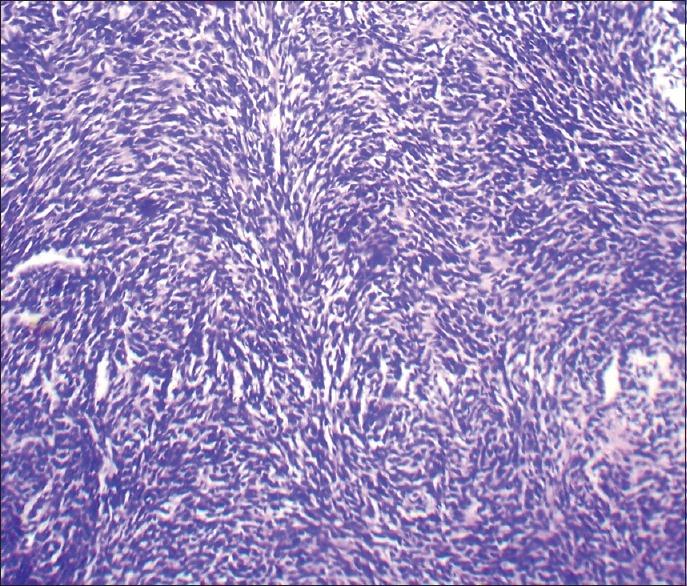

Fibrosarcoma is a malignant tumor of fibroblasts. At one time, it was considered one of the most common soft tissue sarcomas. However, the diagnosis of fibrosarcoma is made much less frequently today because of the recognition and separate classification of other spindle cell lesions that have similar microscopic features. Of all the fibrosarcomas occurring in humans, only 0.05% occur in the head and neck region. Here, we present a case of 22-year-old female patient with the swelling on the left anterior aspect of the face. Histopathologically, the lesion was diagnosed as fibrosarcoma and immunohistochemically, the lesional cells showed positivity for vimentin.

纤维肉瘤是成纤维细胞的恶性肿瘤。曾有一段时间,它被认为是最常见的软组织肉瘤之一。然而,如今纤维肉瘤的诊断频率大大降低,因为其他具有相似微观特征的梭形细胞病变得到了认识并被单独分类。在所有发生于人类的纤维肉瘤中,仅有0.05%发生于头颈部区域。在此,我们报告一例22岁女性患者,其面部左侧前位出现肿胀。组织病理学上,该病变被诊断为纤维肉瘤,免疫组织化学检查显示病变细胞波形蛋白呈阳性。